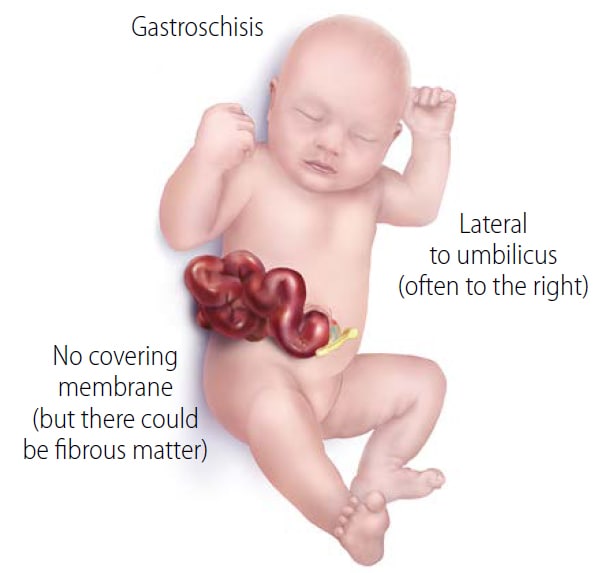

Best Hospital for Robotic Hernia Surgery in Hyderabad : Pace Hospitals